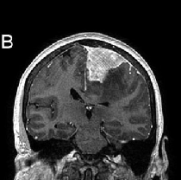

磁共振成像对顶盖肿瘤的显示比CT更可靠,应该在每个患有脑积水的儿童和青少年中进行排序。磁共振成像能够可靠地检测到顶盖肿块,是一种可靠的随访成像方式。对于肿瘤区域对比...

中脑肿瘤的手术入路解读